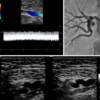

nAdvanced Cardiac Sonographer Registry Review Guide (3rd Edition) Designed by accomplished expert sonographers and ACS imaging specialists, this comprehensive review of basic and advanced echocardiography has been created as a review guide and teaching tool for sonographers preparing to sit for the?Advanced Cardiac Sonographer Registry Exam.

nTopics range from quality assurance to an in-depth review of cardiogenic shock and emergency echo, stress echo, congenital disease, chemotherapy echocardiography, left and right heart function, prosthetic valves, research methods and biostatistics, and interventional echocardiography including the latest technological advances.

nEach lecture has been carefully designed to include a thorough review and clinical application through real video case study presentations.